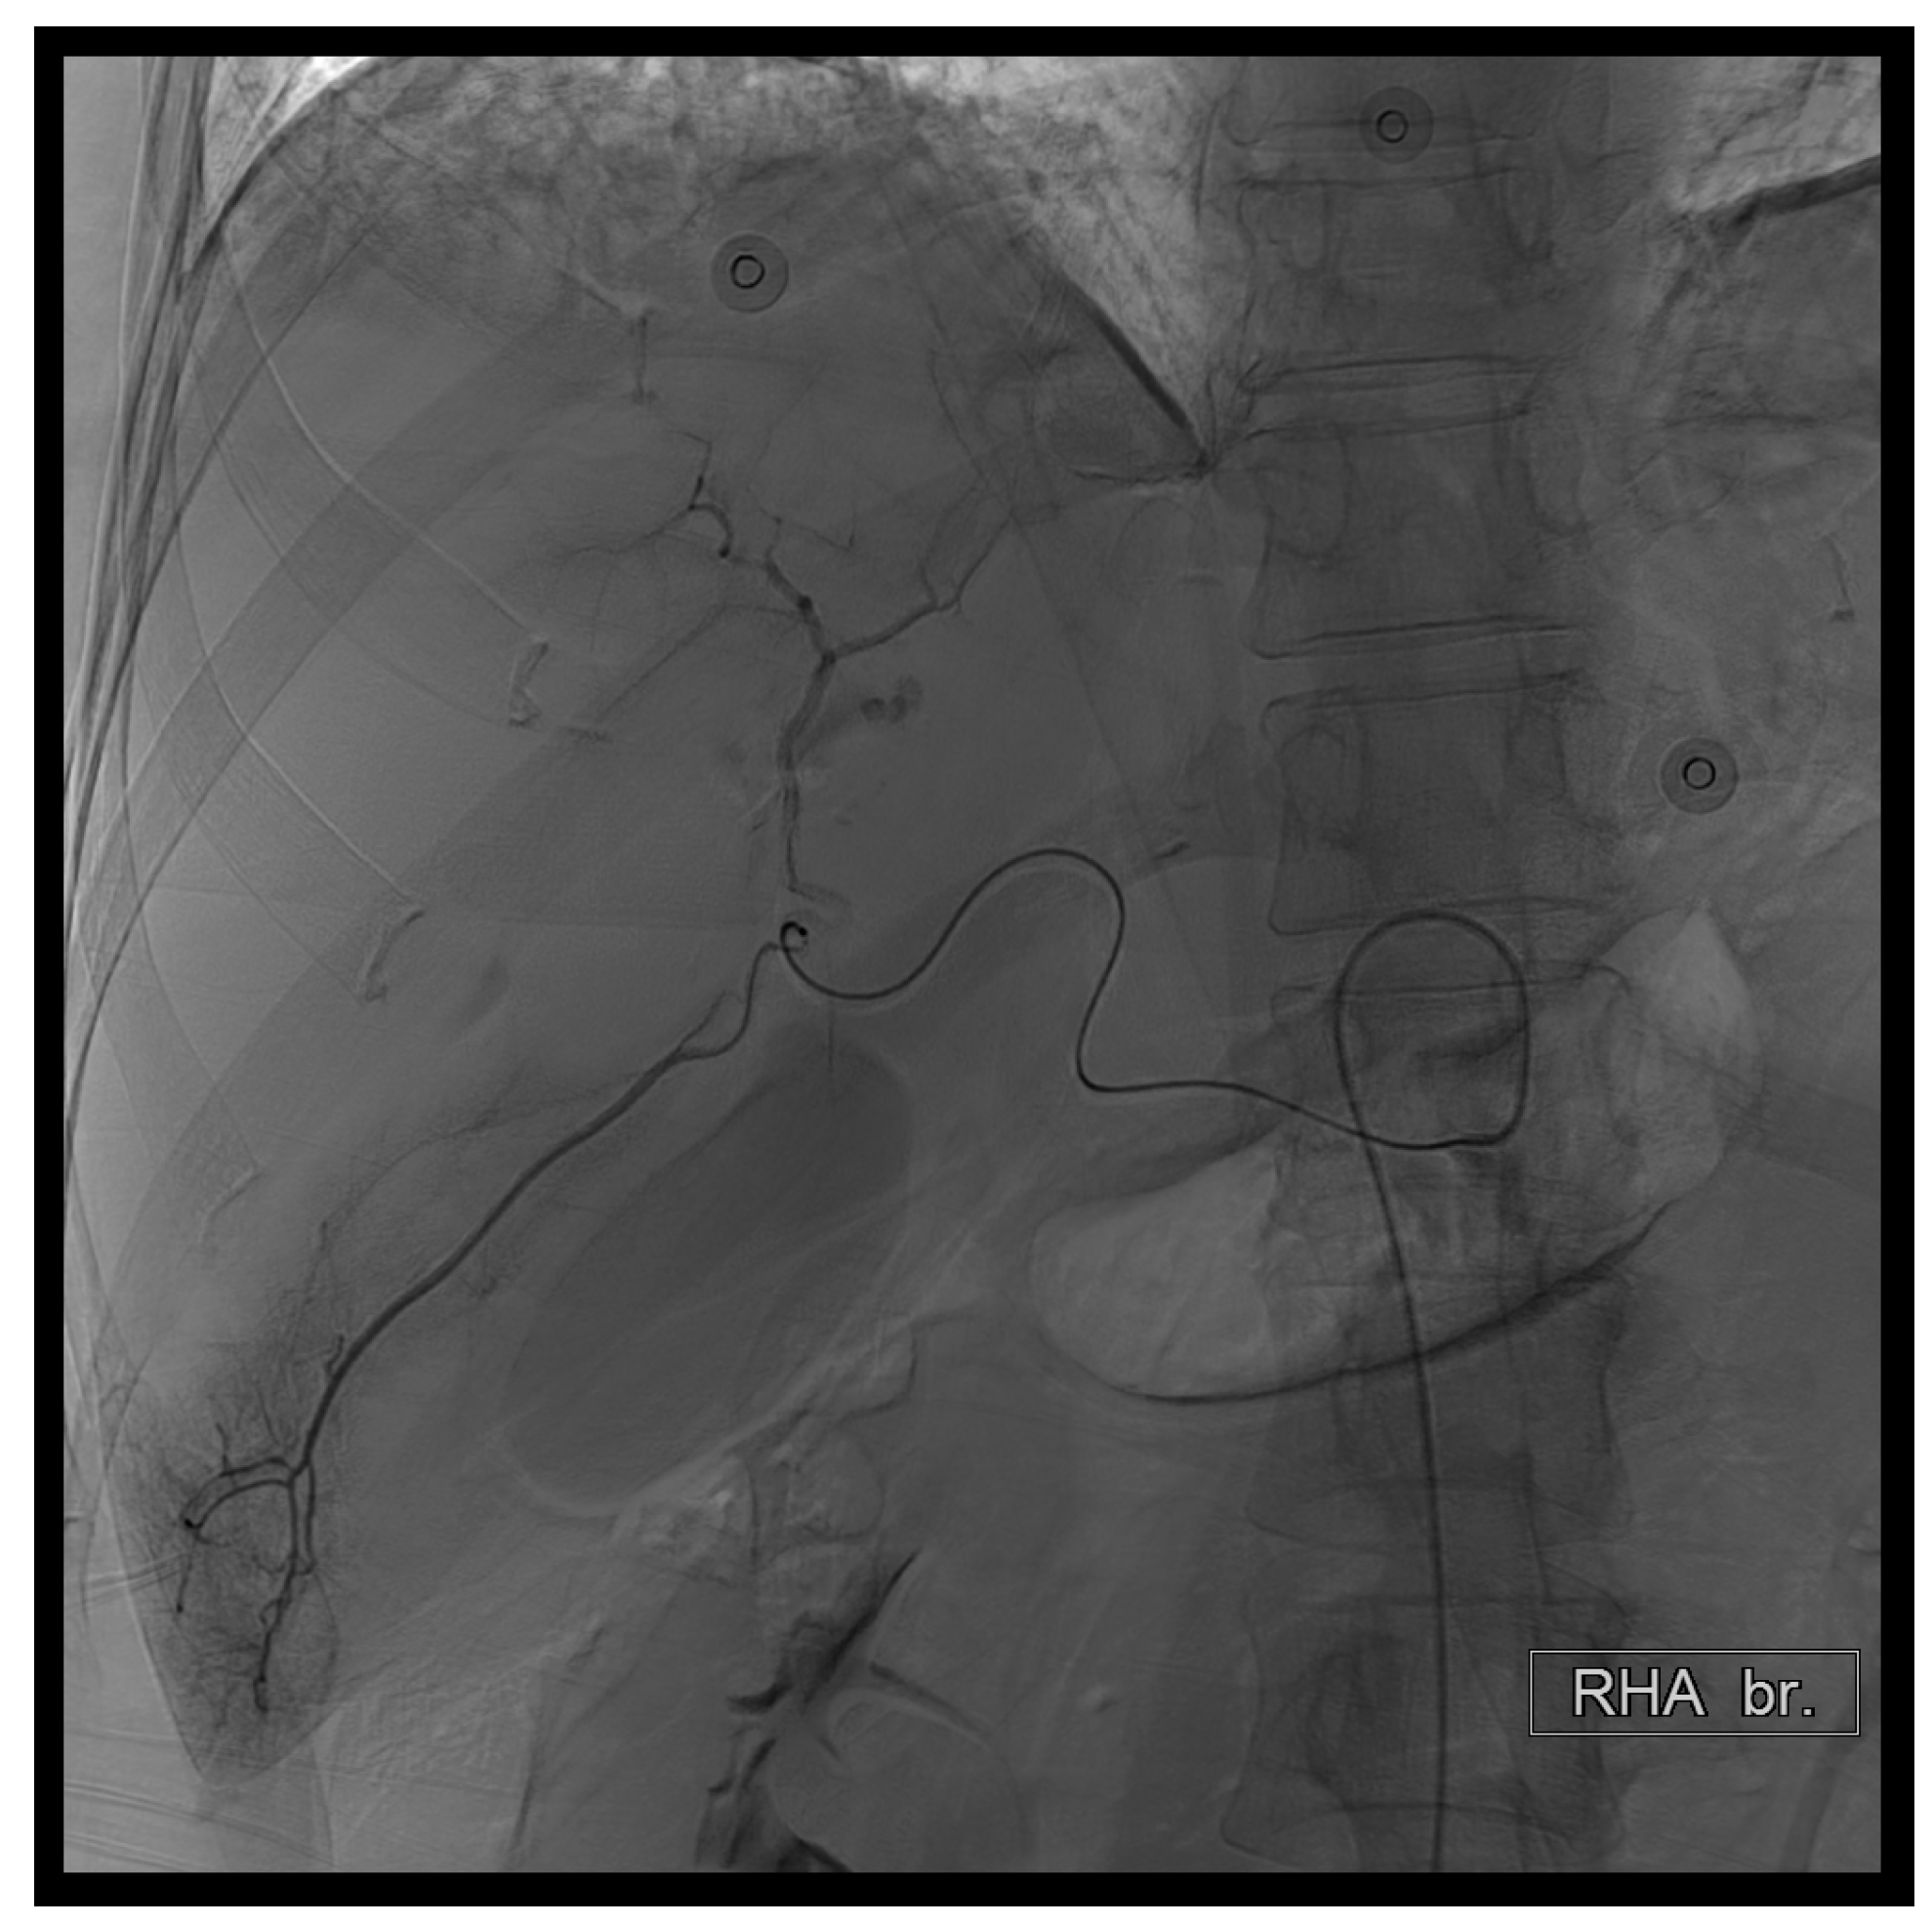

Figure 4. First TAE. Ultimately, due to patient restlessness, we advanced the microcatheter to the depicted position. Subsequently, we performed subselective embolization using a combination of 150–350 micrograms of EG gel diluted with contrast agent.